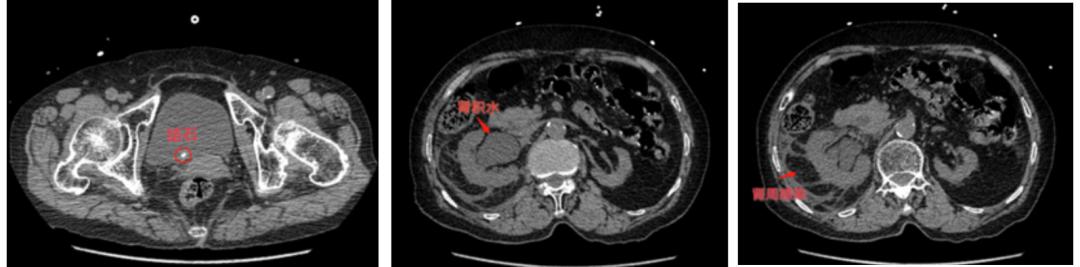

家人连忙将她送到深圳市龙华区人民医院急诊就诊,经CT检查后诊断为“右输尿管结石并肾积水”,感染较重,收至泌尿外科治疗。

手术不到半小时,林奶奶右侧输尿管内的结石被粉碎并取出。林奶奶在术中无明显出血及不适,术后麻醉清醒即可以自行下床走动,复查片子发现结石已经消失无踪。